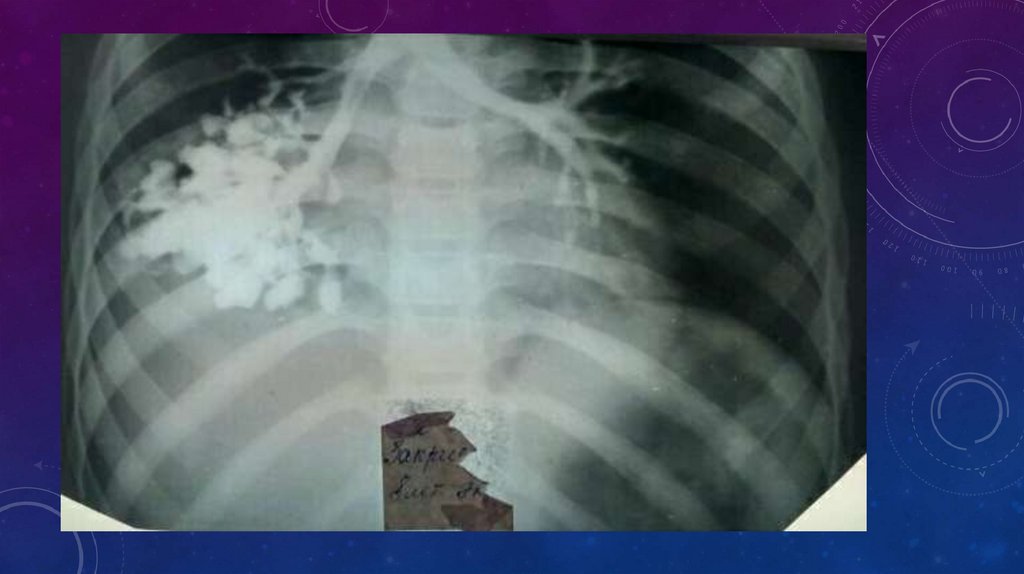

• В первую очередь проводят обзорную рентгеноскопию органов грудной клетки и

рентгенографию. Изменения, обнаруживаемые при этих исследованиях, зависят от

распространенности и тяжести поражения.

• Прямыми и достоверными рентгенологическими признаками бронхоэктазии служат ателектазы

или ячеистые просветления и кольцевидные («сотовидные») тени, соответствующие расширенным

бронхам. Подобные изменения при бронхоэктазии рентгенологически выявляются почти у 1/3

больных. Преимущественно отмечается поражение нижних долей, реже — средней доли и

язычковых сегментов. Соответственно и ателектазы наиболее часто отмечаются в области этих зон

легкого. Обычно ателектазы имеют вид треугольных теней, примыкающих одной стороной к

средостению. Особенно затруднительно выявление ателектаза нижней доли слева. Нужно учесть,

что тень ателектаза в этих случаях накладывается на тень сердца и наружная граница

ателектазированной доли контурируется в виде четкой полосы. При подозрении на ателектаз

средней доли показаны рентгеноскопия и рентгенография в положении гиперлордоза. При

тотальном поражении легкого отмечается некоторое уменьшение соответствующей половины

грудной клетки, сужение межреберных промежутков, затемнение соответствующего легочного

поля, особенно в нижних отделах, смещение средостения в сторону поражения.